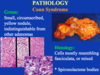

Conn syndrome

aldosterone producing adenoma - primary hyperaldosteronism

indistinguishable from other adenomas

small yellow circumscribed nodule, indstinguishable from others

cells mostly resemble fasiculata or mixed